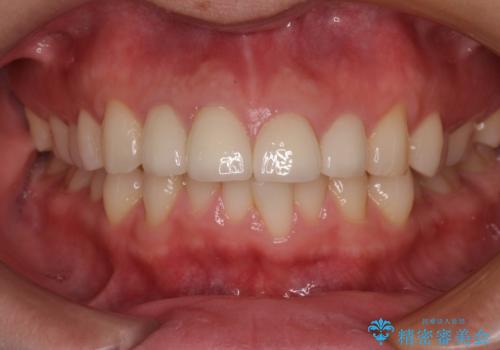

根管治療のやり直しは希望されなかったため、土台のやり替えと、より自然なオールセラミッククラウンへのやり替えを行いました。

自然できれなオールセラミッククラウンになり、とても満足されました。